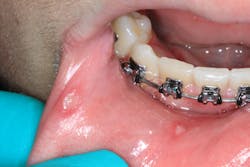

Patient: 16-year-old male

- Multiple lesions salt-and-peppered in a generalized fashion throughout the entire oral cavity

- Lesions are white with red borders

- Gum tissues swollen

- Light palpation/touching of the lesions results in bleeding and pain